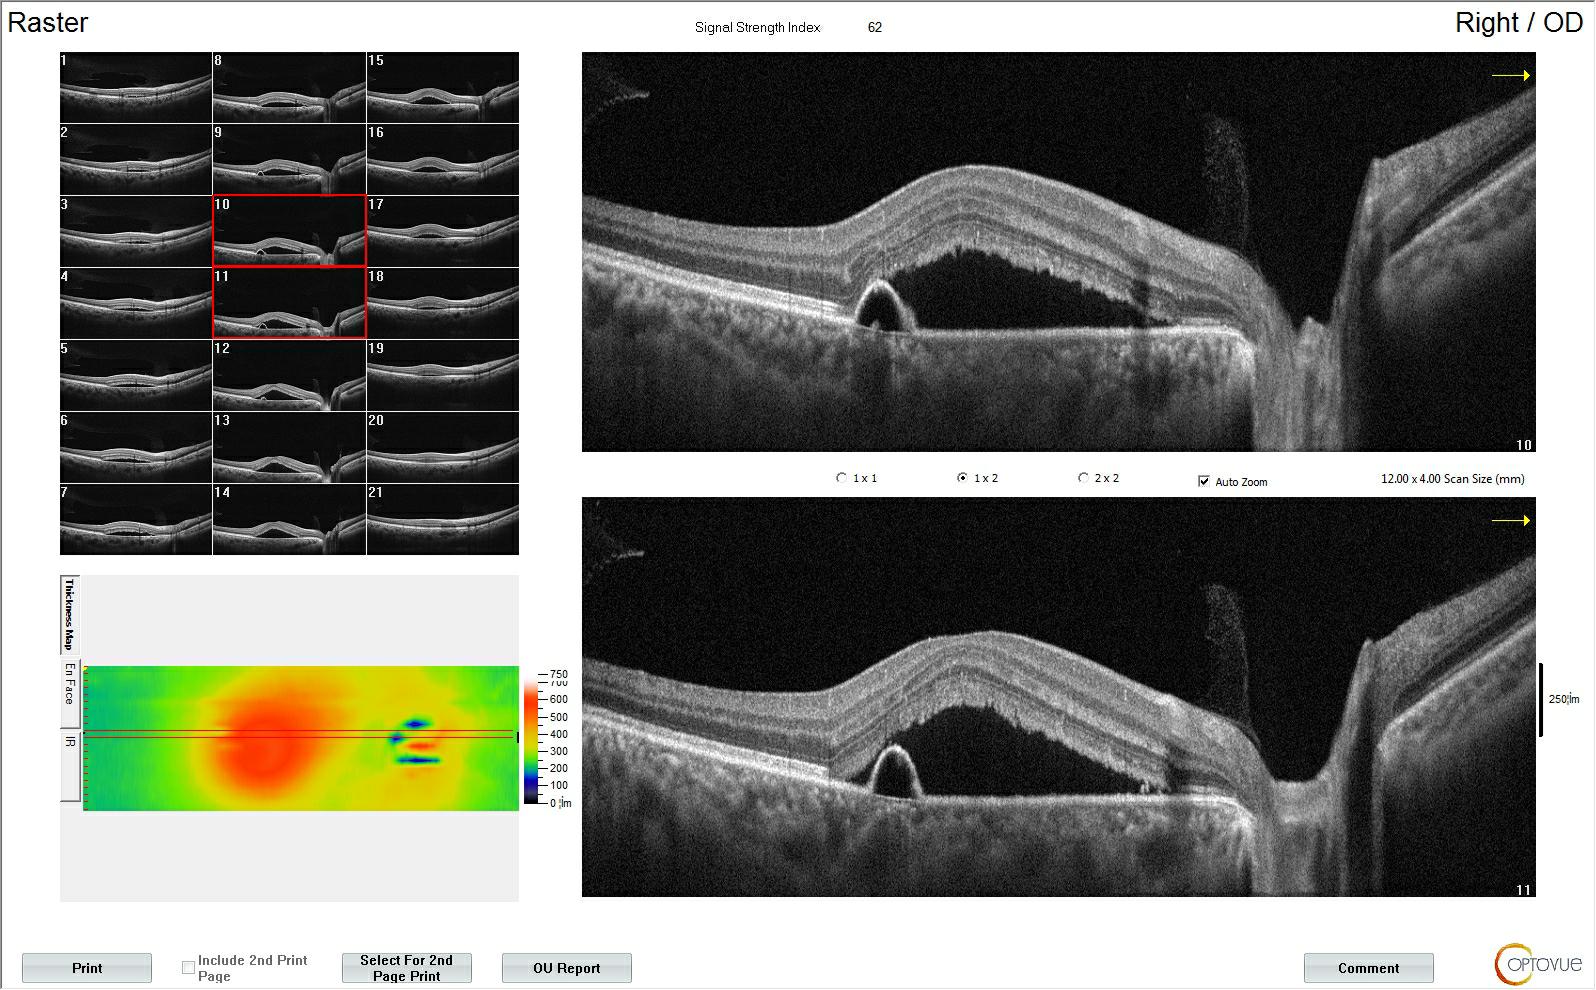

2、CNV治疗评估:血流面积测量,血流密度测量。

3、评估无灌注区域:无血流面积测量。

抗VEGF 治疗CNV后的无创随访: